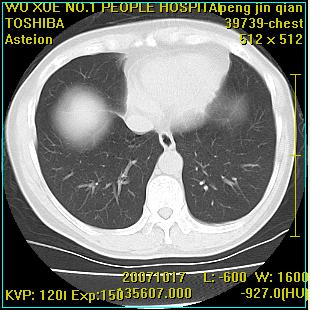

标题: CT10148:男,56岁,咳血。 [打印本页]

标题: CT10148:男,56岁,咳血。

左肺上叶尖段占位性病变,考虑肺癌.癌性空洞,并双肺转移灶及纵隔淋巴结转移

左肺上叶尖后段较大团块影,边缘光滑,内见不规则裂隙样空洞,周围明显见细小结节及渗出,与肺门方向结构紊乱,另:左上叶尖段外侧 舌叶内侧 右上叶尖段及下叶背段均见片状致密影。考虑:继发性肺结核伴空洞形成!

左上肺后壁空洞,内壁不规则,可见壁结节;左上叶尖段外侧 舌叶内侧 右上叶尖段及下叶背段均见片状致密影。考虑:左肺肺癌并两肺继发性肺结核?

左肺上叶尖段占位性病变,

考虑肺癌.癌性空洞,并双肺转移灶及纵隔淋巴结转移